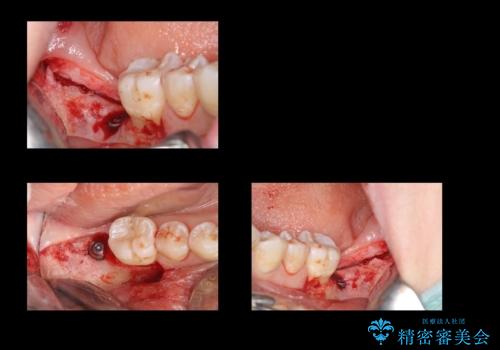

抜歯を行い、インプラントを入れていきました。

炎症で骨が少なかった場所には骨補填材を置いています。